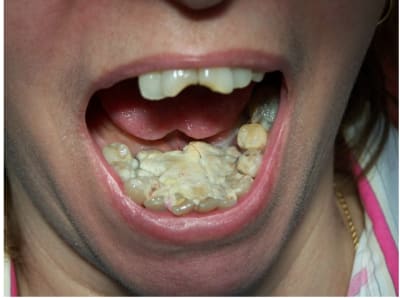

Championat de France de bouche pourrie, c'est parti !

sans avoir l'intention de me moquer, parce que chacun rencontre ses propres difficultés au quotidien, je vous propose d'envoyer vos meilleurs photos de bouche la plus dégueu que vous ayez rencontré.

je commence:

vu ce matin (j'ai encore la nausée, l'odeur est tenace, même avec les fenêtres ouvertes)...

l'assistante; de quand date votre dernier rdv ?

" ho! ça fait un bail, mais comme je n'ai aucun problème je ne viens pas"

moi; et mis à part cette petite douleur qui vous empèche de dormir depuis trois jours, tout va bien ?

" oui, c'est parfait"

Merde, vous attaquez trop fort.

J'en vois jamais des comme ça !!!!!

50 ans diabetique ...